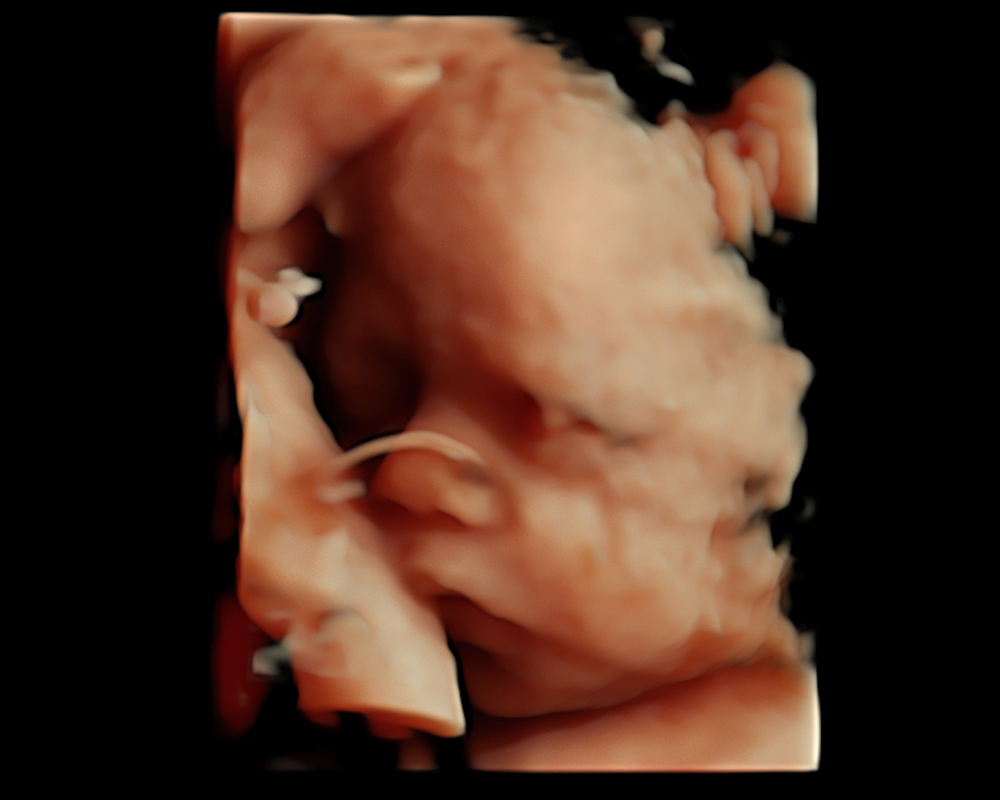

Eco Anatómico 4D

Realizado entre las semanas 20 y 30, el Eco Anatómico 4D, es un estudio que permite una valoración detallada del crecimiento, órganos y estructuras de bebé. Este eco es crucial para la detección temprana de malformaciones congénitas. Si la posición de bebé y las condiciones nos permiten, podemos llevarnos un hermoso recuerdo al tomar fotografías en 4d.